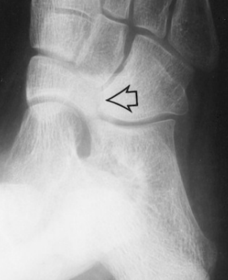

| What disease is this? What does the arrow indicate? | Rheumatoid arthritis. Arrow = Bone erosion secondary to inflammation of retrocalcaneal bursa. |